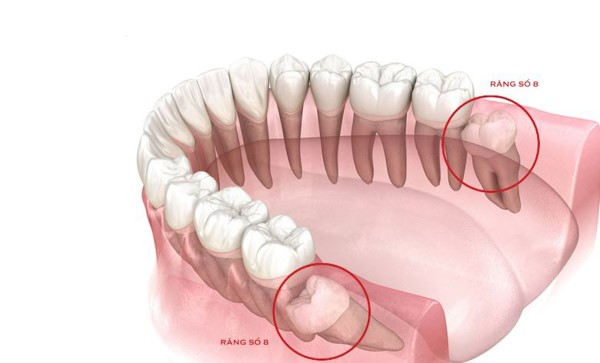

Răng số 8, còn được gọi là răng khôn, là những chiếc răng cuối cùng mọc trong khoang miệng, thường xuất hiện khi chúng ta ở độ tuổi từ 17 đến 25. Răng khôn có thể mọc thẳng hàng hoặc mọc lệch, mọc ngầm, thậm chí là không mọc lên được. Việc nhổ răng số 8 thường là giải pháp cuối cùng, được thực hiện khi răng khôn gây ra các vấn đề về sức khỏe răng miệng. Bài viết này sẽ cung cấp thông tin chi tiết về chi phí nhổ răng số 8, các yếu tố ảnh hưởng đến chi phí, quy trình nhổ răng, cũng như các thông tin bổ ích khác để bạn có thể đưa ra quyết định đúng đắn cho tình trạng răng miệng của mình.

Trước khi đi sâu vào chi phí nhổ răng số 8 bao nhiêu tiền, chúng ta sẽ tìm hiểu trước về răng số 8 là gì? Răng số 8 là những chiếc răng cuối cùng trong khoang miệng, mọc ở vị trí phía sau cùng của hàm, thường xuất hiện ở tuổi từ 17 đến 25. Tuy nhiên, đôi khi răng khôn có thể mọc muộn hơn hoặc thậm chí không mọc.

Răng khôn có thể đóng vai trò quan trọng trong việc nhai thức ăn và giữ cho hàm răng của bạn chắc khỏe. Tuy nhiên, trong thực tế, nhiều người không sử dụng răng khôn để nhai vì chúng mọc lệch, mọc ngầm hoặc không đủ không gian trong hàm.